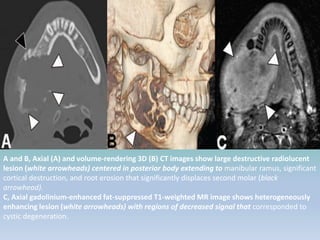

A and B, Axial (A) and volume-rendering 3D (B) CT images show large destructive radiolucent

lesion (white arrowheads) centered in posterior body extending to manibular ramus, significant

cortical destruction, and root erosion that significantly displaces second molar (black

arrowhead).

C, Axial gadolinium-enhanced fat-suppressed T1-weighted MR image shows heterogeneously

enhancing lesion (white arrowheads) with regions of decreased signal that corresponded to

cystic degeneration.